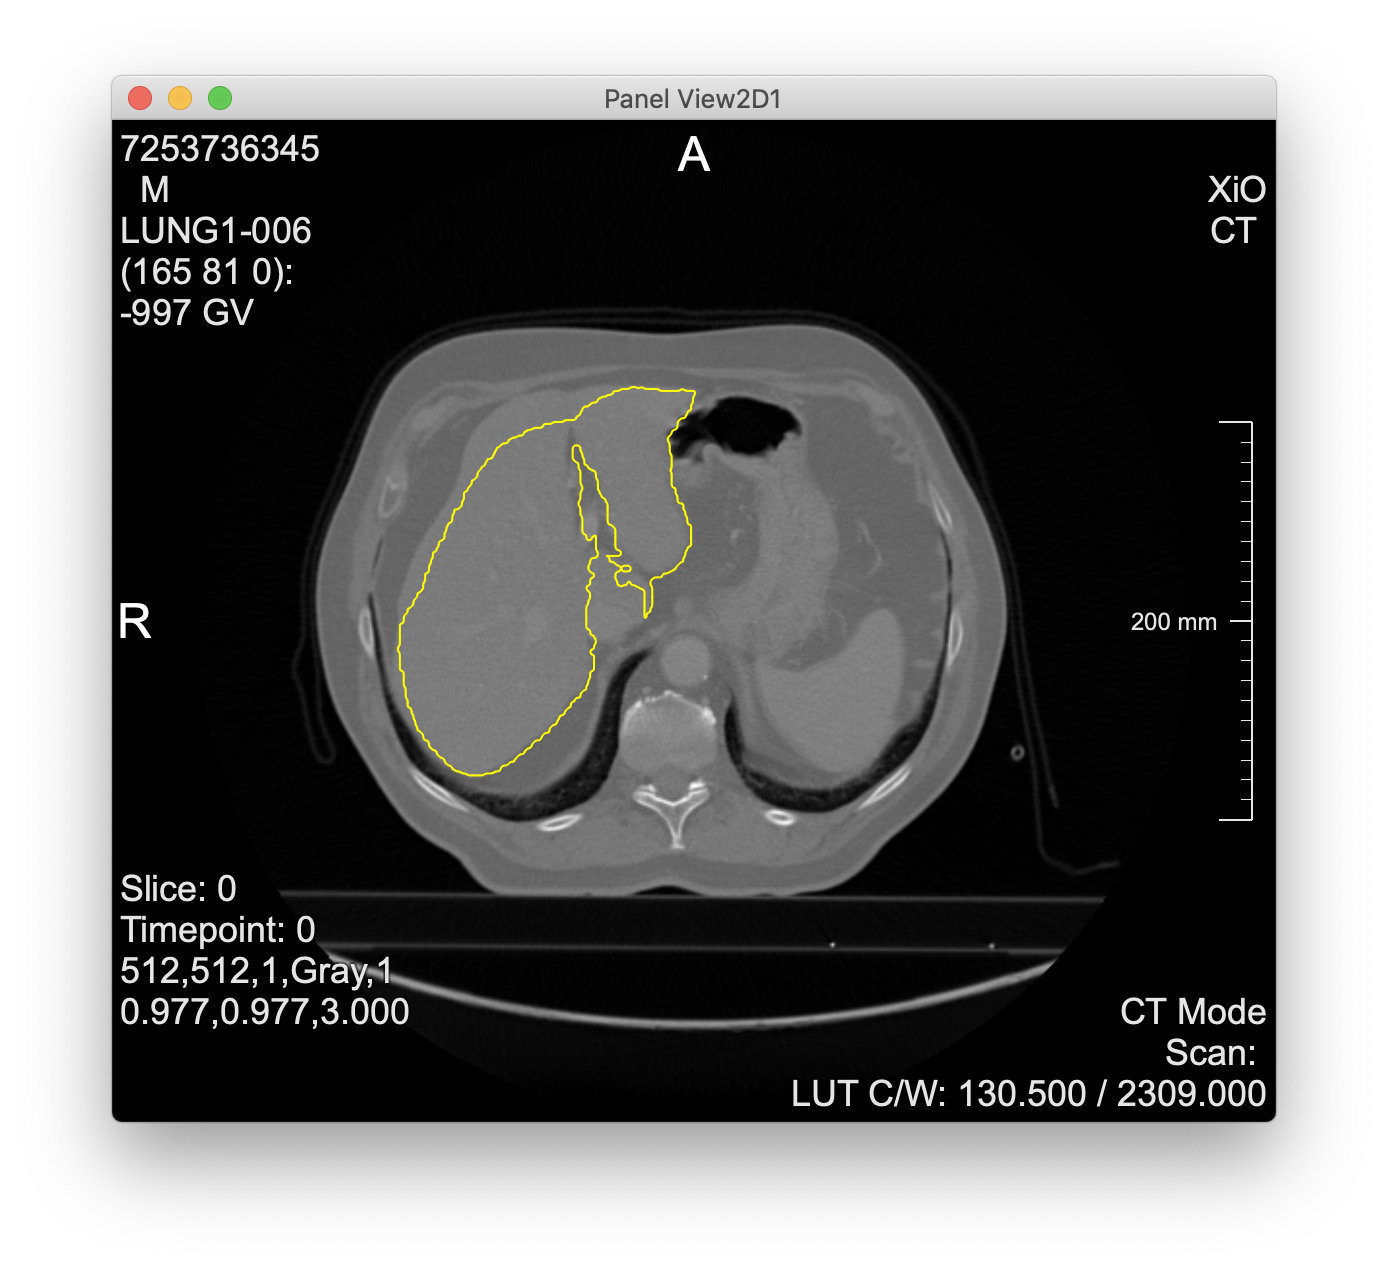

- cascaded-fcn-liver is an interesting model (from the organizers of the LiTS challenge)

- Evaluation of cascaded-fcn-liver

- takes a single CT slice as DICOM file via a form-encoded POST request

- returns contours as voxel coordinates in JSON format

- screenshot from MeVisLab experiments below

- “cascaded” = two networks for liver + tumor segmentation, but the API runs only the first (the second is included, but execution is left to the user)

Liver contours computed via the cascaded-fcn-liver model parsed and visualized in MeVisLab: